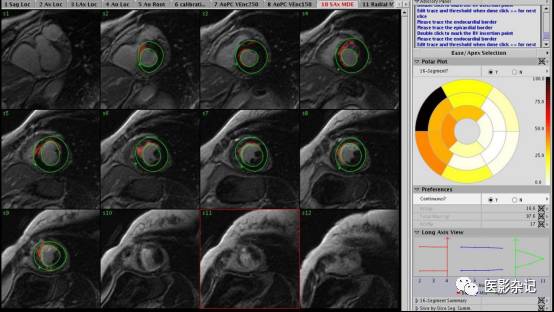

其中,心脏功能学检查是MRI的一项重要应用,其过程大致为:采用电影采集扫描获取并显示心脏MRI心脏动态图像,也就是在一个心跳周期中的多个时相的心脏三维影像;采用手动、半自动或全自动方式勾画心室内外侧壁最大舒张末期和最大收缩末期轮廓,如果能够勾画整个心动周期舒收的每一时相更好;通过勾画的轮廓用心功能分析软件包计算出心室容积、肌块和心功能有关参数绘出心室容积及容积的变化率曲线图;从而进一步根据心室内外心肌壁的轮廓变化来分析及评价心肌厚度,并且以图、表形式显示心肌厚度的变化。

在MRI心脏功能学和灌注检查影像分析中,都会用到心脏分区和牛眼图功能。同时,会大量使用电影播放(Cine)功能。

*左心室短轴位冠脉心肌供血分区示图: 供血分区:0-3、13-15 左前降支供血区,4-7 左回 旋支供血区,8-12 右冠供血区。心肌壁划分:前壁0-3;侧壁4-7;下后壁8-11;间壁12-15。

*心肌灌注牛眼图

GE CardiacVX 软件包提供电影播放功能,用于辅助查看多断层、多相位MRI影像。GE Cardiac Function Analysis心脏功能分析模块,具备每博输出量(stroke volume)和射血分数(ejection fraction)计算功能,采用半自动方式分割心肌等组织。

*GE CardiacVX

Siemens Syngo.MR Cardiac 4D Ventricular Function 模块提供基于手工或自动的左右心室容积计算,并内置工作流程向导。

*Siemens Syngo.MR Cardiac 4D Ventricular Function